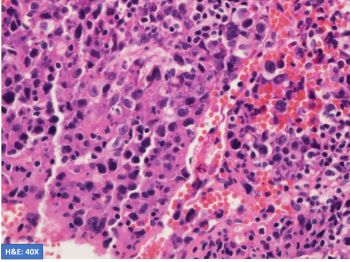

A 52-year-old man with HIV presents with weight loss and supraclavicular mass. Biopsy shows large, atypical cells with the following phenotype: CD45+, CD20-, PAX5 weak, CD3-, CD15-, CD138-, EBER-ISH+. H&E and stains for CD30 and CD79a are shown.

This is a case of EBV-positive diffuse large B-cell lymphoma associated with immune deficiency with an unusual phenotype. B-cell markers are downregulated with negative CD20 and weak expression of PAX5 and CD79a. The unusual phenotype combined with CD30 positivity raises the possibility of Classic Hodgkin lymphoma (CHL). However, the neoplastic cells are positive for CD45 and negative for CD15, making CHL unlikely. Plasmablastic lymphoma was excluded by CD138 negativity.